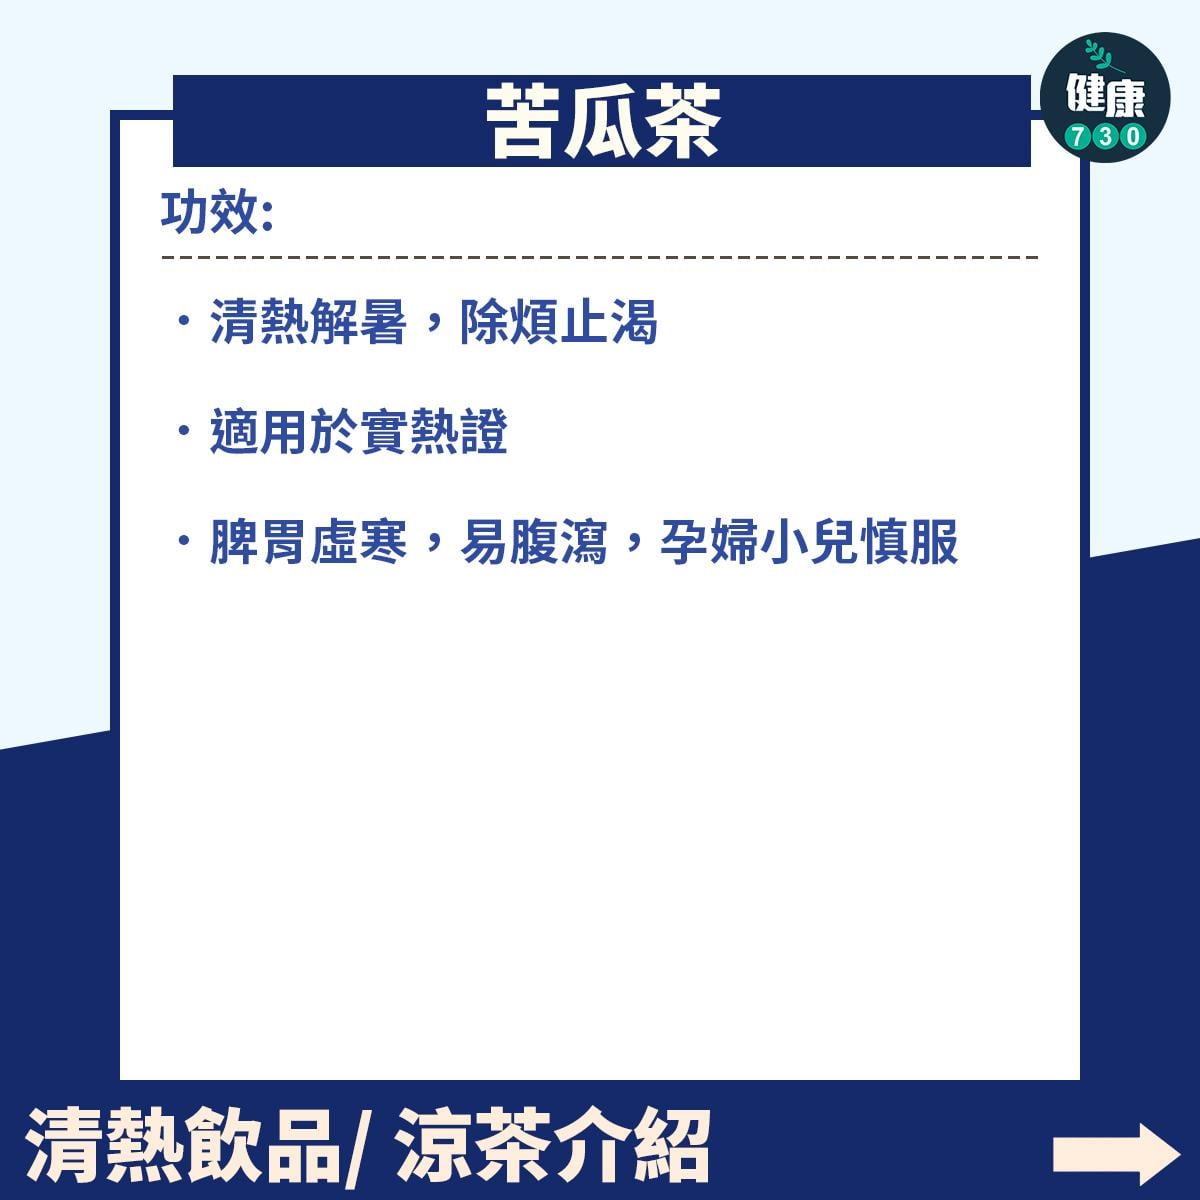

雖然苦瓜好處很多,但亦不要食過量,否則有可能引起噁心、嘔吐等症狀,苦瓜味苦性寒涼,胃寒體虛者要注意食用量。另外,苦瓜中的奎寧有機會刺激子宮收縮,或致流產,雖然含量極少適量食用並無大礙,惟孕婦仍應多加留意,盡量少吃為妙。